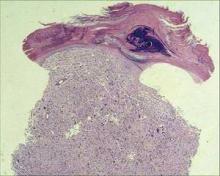

Photo credit: Dr. Henry W. Randle

Histologically, AFX is a nonencapsulated cellular tumor, contiguous with the epidermis.

Visually, AFX usually looks like a rapidly growing red nodule, often ulcerated, on the sun-damaged head or neck skin of an elderly patient. It is twice as common in men as in women. Histologically, it’s a nonencapsulated cellular tumor, contiguous with the epidermis, with pleomorphic and atypical cells. It often has spindle-shaped cells with prominent, vesicular nuclei.